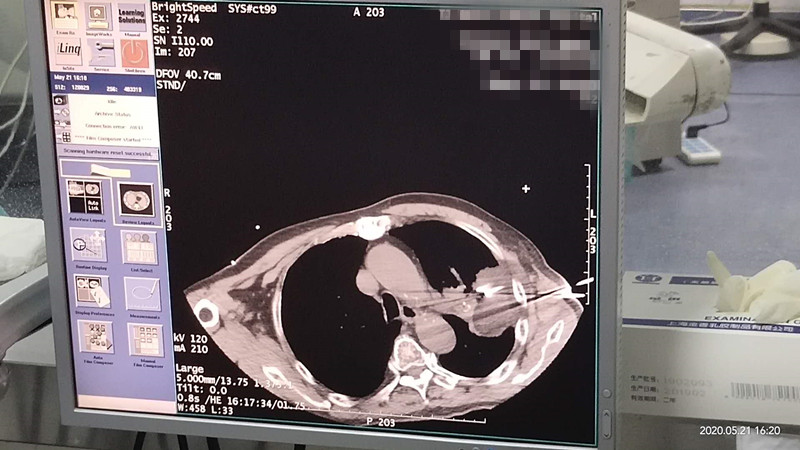

76岁肺部氩氦刀冷冻消融